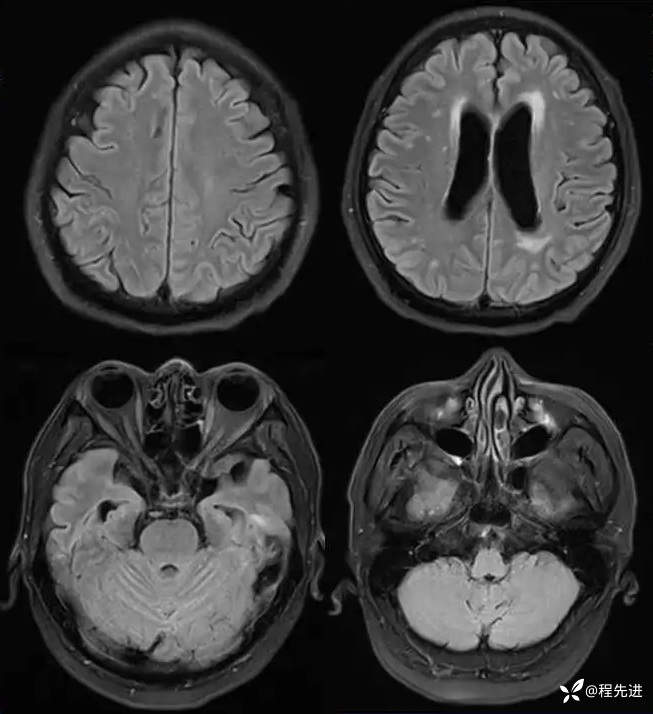

MR平扫+增强: